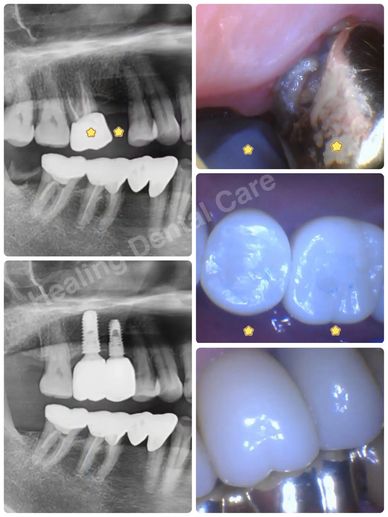

Gold crown with recurrent decay was extracted. An immediate implant placement was done on the extraction site with another implant placement on the adjacent missing tooth area. Then, two implant-supported crowns were restored.